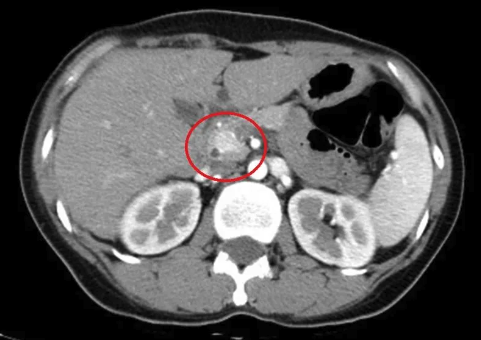

王子源醫師安排患者住院檢查,發現72小時禁食試驗後出現低血糖,再加上血中胰島素及「C-胜鏈胰島素」(C-peptide)偏高,屬於內源性胰島素分泌過多,進一步檢查後發現胰臟的頭部有一顆約1.4公分的腫瘤,確診為「胰島素瘤」,經由手術切除後血糖逐漸恢復正常,脫序行為也不再發生,讓家屬感動表示:「撿回來了!」